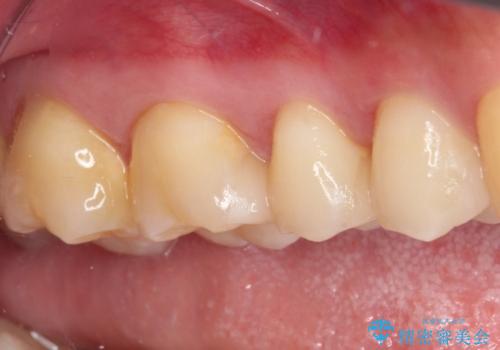

詰め物が外れた セラミックインレー修復

- 以前治療した詰め物が外れてしまい、冷たいものがしみることを主訴として来院された患者様です。

むし歯がないことを確認し、セラミックインレーにて修復するととしました。

適合の良いセラミックインレーの装着により、冷たいものがしみる症状はなくなりました。